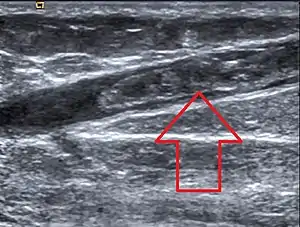

Clot in the greater saphenous vein; oral estrogen is associated with increased risk of venous blood clots due to increased liver formation of vitamin K-dependent clotting factors.

Effects of hormone replacement therapy on venous blood clot formation and potential for pulmonary embolism may vary with different estrogen and progestogen therapies, and with different doses or method of use.[18] Comparisons between routes of administration suggest that when estrogens are applied to the skin or vagina, there is a lower risk of blood clots,[18][46] whereas when used orally, the risk of blood clots and pulmonary embolism is increased.[47] Skin and vaginal routes of hormone therapy are not subject to first pass metabolism, and so lack the anabolic effects that oral therapy has on liver synthesis of vitamin K-dependent clotting factors, possibly explaining why oral therapy may increase blood clot formation.[48]